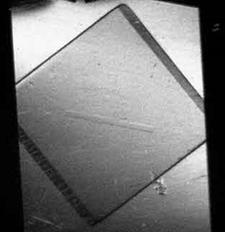

На Курчатовском источнике СИ были проведены исследования биоптатов костной ткани человека, предоставленные Центральным институтом травматологии и ортопедии им.Н.Н.Приорова (ЦИТО). Биоптаты представляют собой небольшие фрагменты, объемом менее одного кубического сантиметра, извлеченные посредством операции из кости и помещенные в формалин. На рис.5 показаны снимки, сделанные методом рефракции (а) и поглощения (б). Видно, что структура кости на рис.5,а проявляется значительно лучше, чем на рисунке 5,б. На верхнем рисунке хорошо виден внешний (кортикальный слой) кости, а также внутренний, который состоит из продольных слоев (трабекул) размером до нескольких сотен микрон. Здесь использование синхротронного излучения приобретает особое значение, потому что другие методы для оценки прочности кости оказываются малоприменимыми. Хотя с помощью электронного микроскопа, дающего очень высокое пространственное разрешение, можно увидеть в кости кристаллы кальцита размером около 1 мкм, но в практической медицине это пока не нашло широкого применения. На синхротронных пучках размеры и ориентацию таких кристаллов удается определять с помощью электронной спектроскопии.

Рис. 5. Изображение биоптата кости человека, полученное методом рефракции (а) и поглощения (б) на Курчатовском источнике СИ.